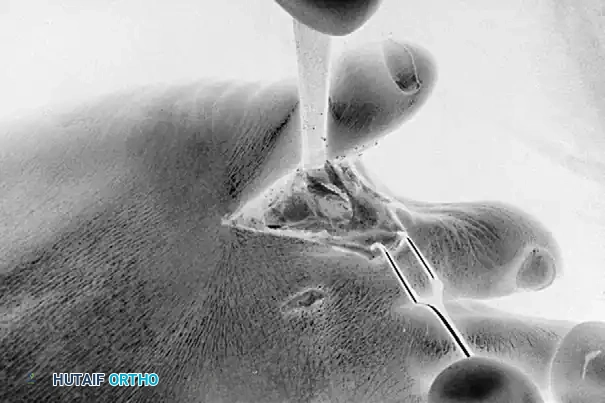

Exposure of the web space and meticulous resection of the lateral base of the fourth proximal phalanx using a sharp osteotome or sagittal saw.

Exposure and resection of the medial aspect of the proximal fifth toe. Note the careful protection of the surrounding soft tissue envelope.

Following the initial resection, the surgeon must manually compress the fourth and fifth toes together to simulate a weight-bearing, shod foot. The web space is deeply palpated to determine if any residual bony impingement exists. If the resection seems inadequate or if impingement persists, the opposite bony offender must also be resected.